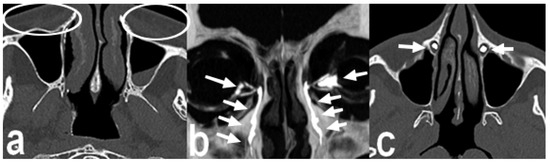

Background: Conventional CT–dacryocystography (CT-DCG) requires canalicular cannulation and forced contrast injection, which may distort anatomy and cause discomfort. This study describes a non-cannulated CT-DCG protocol using dropwise iodixano...